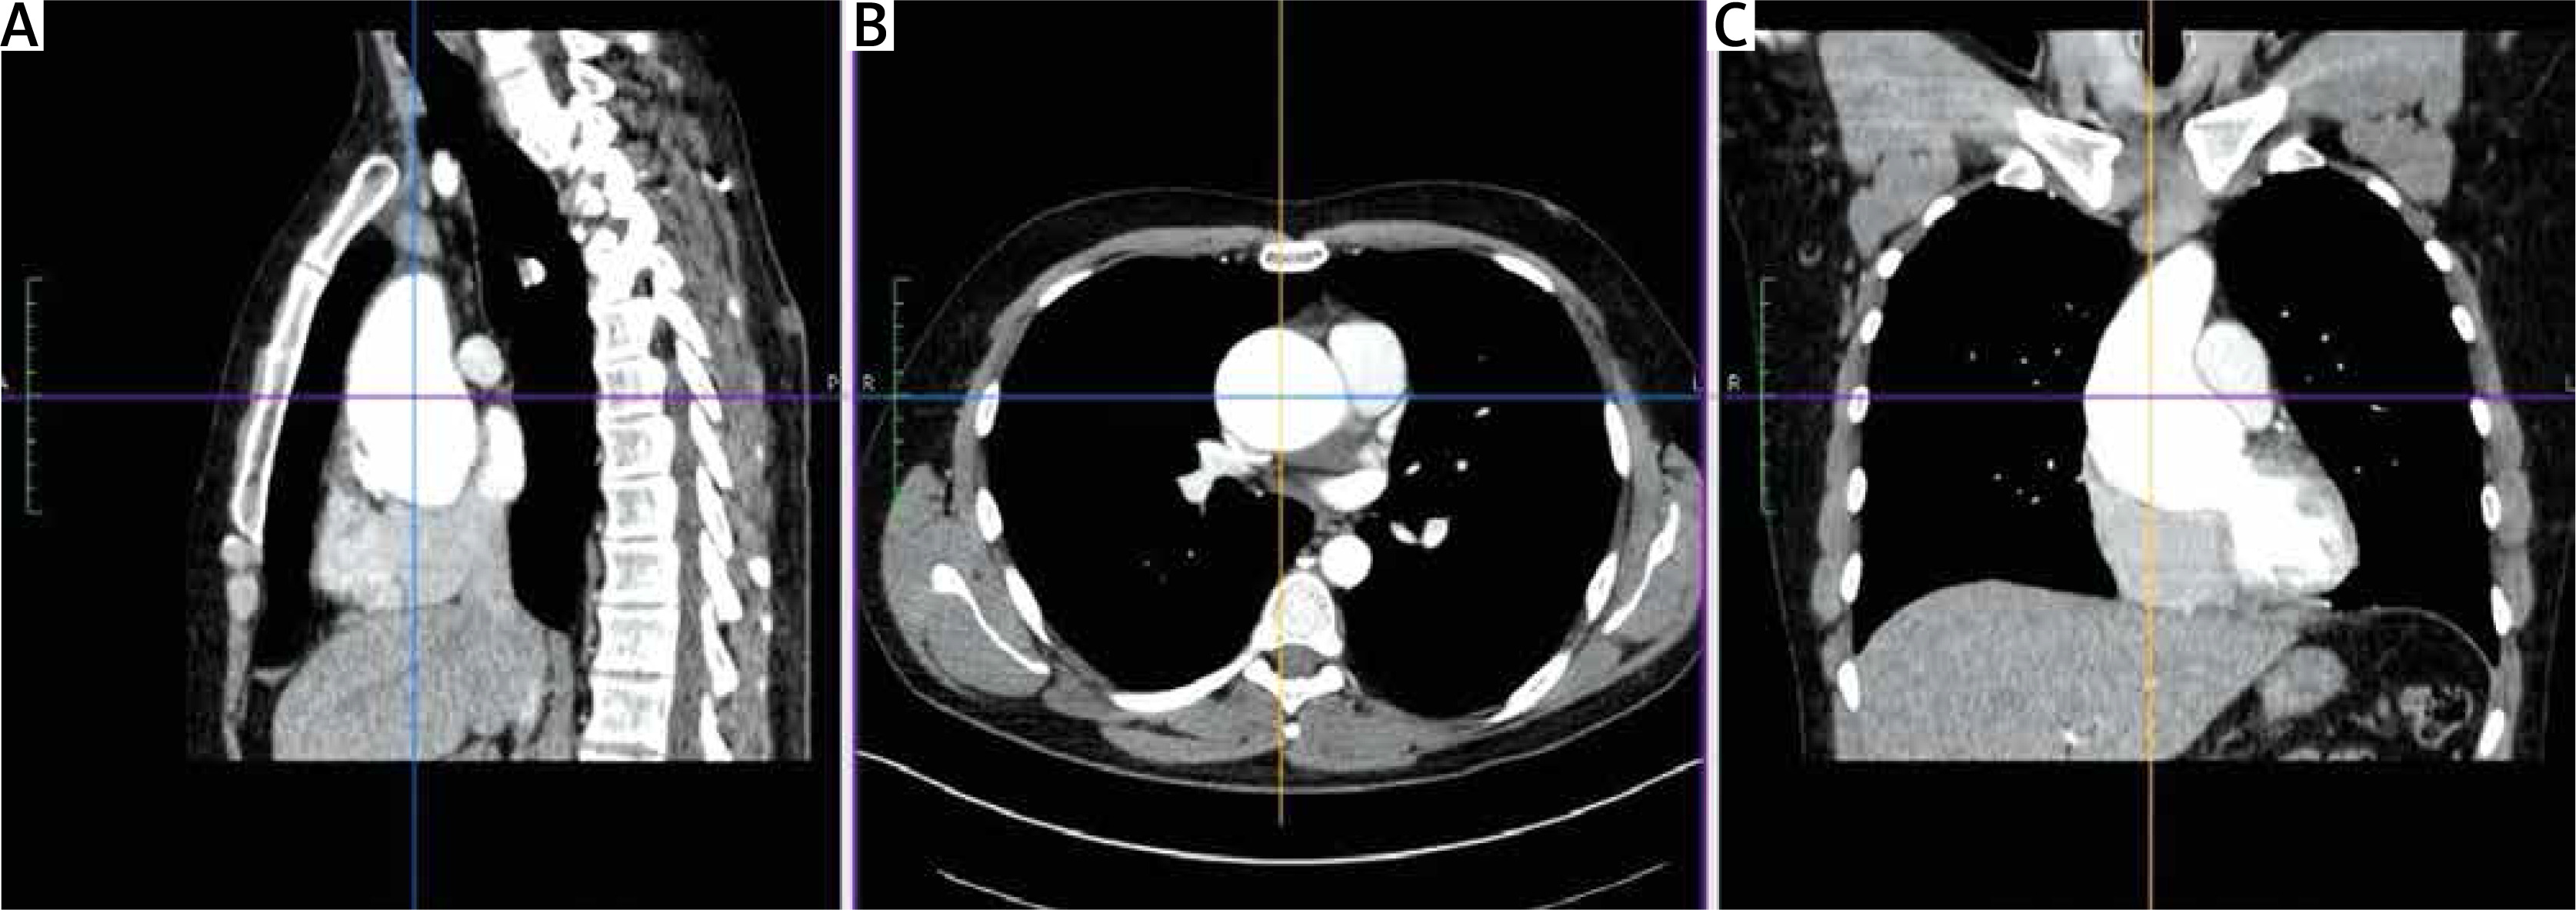

The key element of proper preparation of the patient for the surgery is the performance of chest computed tomography (CT) with 3D reconstruction to assess the ratio of the aneurysm to the sternum surface and the type of aortic position (right, central, left). Such assessment facilitates and streamlines the decision process about the skin incision site and the transverse cut of the sternum (Figure 1). Transesophageal echocardiography remains the most important functional examination in the assessment of aortic valve insufficiency and is essential in the intraoperative assessment of the competence of the performed reimplantation (Figure 2).